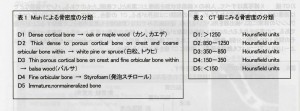

その際、クリニックでは、院内で撮影したCTをインプラント治療シュミレーションソフトで分析し、下記のような評価法と対比させ、骨の状態を判断に用いています。

骨の評価を5段階に分類し、その情報をもとに、手術方法を微妙に変化させます。